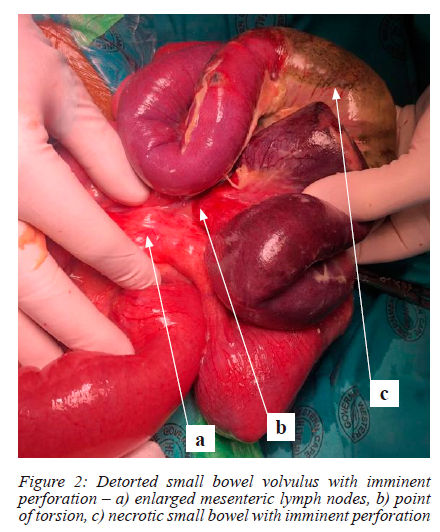

The patient was resuscitated with intravenous fluids over four hours with marked improvement in his hemodynamic status and blood gas analysis. Despite analgesia, his abdominal exam remained unchanged. He was then scheduled for an emergency exploratory laparotomy where a small bowel volvulus with a segment of necrotic bowel and imminent perforation affecting the mid-ileum was noted (Figure 2). Intestinal worms were felt throughout the small bowel and large mesenteric lymph nodes were also present. The bowel was detorted, and the intestinal worms milked towards the cecum. Approximately 20 cm of ischemic and necrotic small bowel was then resected. An end-to-end anastomosis was performed with a running Vicryl 4/0 suture.

Histology of the resected small intestine showed transmural necrosis and infarction compatible with an ischaemic aetiology. Ascaris infection was present. The mesenteric nodes included in the resection demonstrated reactive lymphoid hyperplasia.

In our case report, the most obvious cause for the volvulus were worms causing a mass effect on the small intestine and resulting in a volvulus. Although the most common site of volvulus due to intestinal worms has been reported to be at the ileocecal junction,5 in our case the volvulus was located in the mid-ileum. Other case reports with small bowel volvulus due to intestinal worms have also noted large mesenteric lymph nodes; these nodes may play a minor contributing factor to the volvulus by acting as a pivot point.7